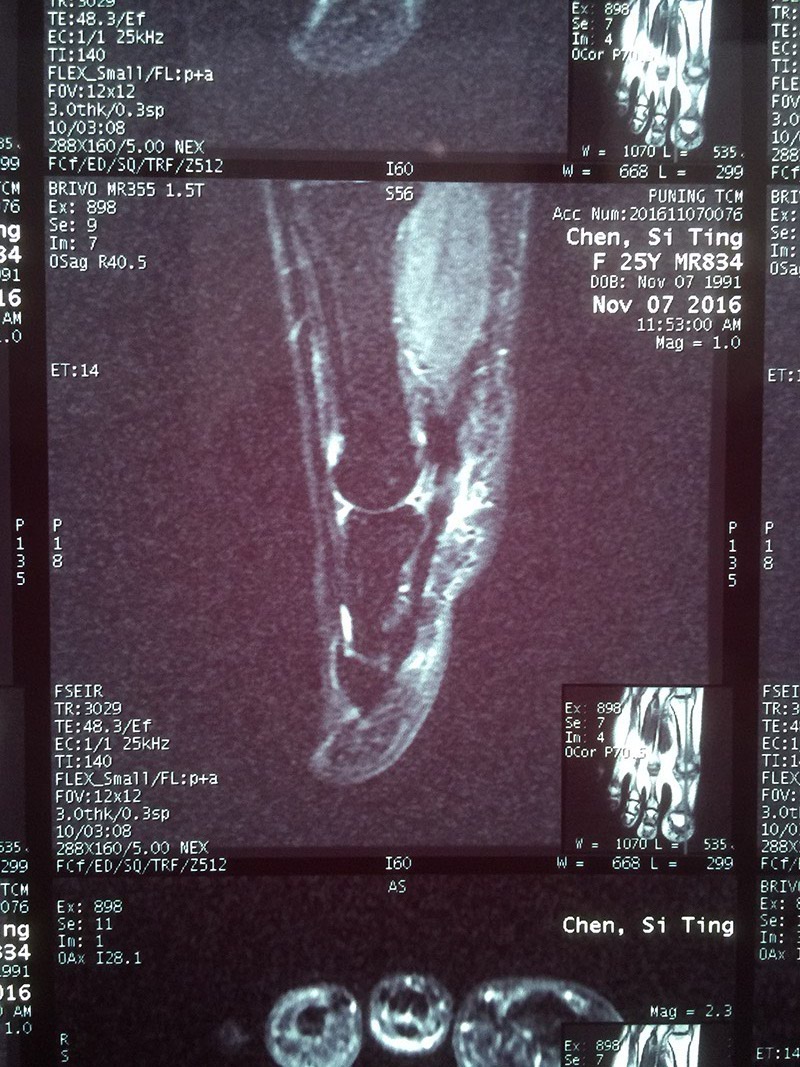

11月7日前往当地某中医院住院治疗,院内行右足脚趾MR提示:局部软组织水肿,血沉、血常规、C反应蛋白均提示无明显异常,医生给的诊断是肌腱炎,于是又继续抗感染治疗6天,陈小姐依然还是感觉大趾底部刺痛,行动不便。

陈小姐与其父亲搀扶下来到威尔医院,林医生仔细询问了其病史,并为其作了体格检查:右足大趾跖屈无力,局部按压有刺痛感。根据其检查结果及体格检查,林医生给出诊断是:右足指屈肌腱损伤。现在已错过最佳治疗时机,建议局部进行封闭治疗,但陈小姐拒绝,林医生建议其2个月内完全制动,使受损的肌腱自行慢慢修复,局部使用冰敷治疗,减轻局部组织水肿带来的疼痛刺激。